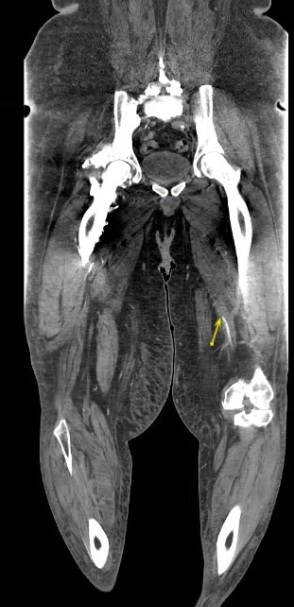

A 37 yo M w/ a PMH of type 2 DM and non-ischemic cardiomyopathy presents to the ED with 6 days of progressively worsening L lower extremity pain. On exam, the L lower leg is slightly erythematous/edematous and is cool to touch when compared to the R. There is decreased sensation in the L foot. On Doppler exam, the L PT pulse is normal, but DP pulse is weak. A CTA runoff is obtained. What's the diagnosis? (scroll down for answer)

Answer: Occlusion of the L superficial femoral artery